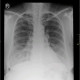

Pasien sesak sudah bertahun tahun, memberat sejak kemarin. Riwayat batuk lama menahun, riwayat batuk darah disangkal. Pengobatan TB di sangkal. Mohon konsul bacaan radiologi ini dok. Terimakasih sebelumnya dokter

Untuk Interpretasi Rontgen Toraks yang dokter sampaikan:

Trakea yang tidak berada di garis tengah menandakan adanya deviasi trakea, Ukuran jantung yang terlihat normal, hemidiafragma kanan lebih tinggi dibandingkan hemidiafragma kiri, ditemukan sudut yang menumpul dibagian sebelah kiri sehingga bisa dicurigai adanya efusi pleura. Telihat adanya proses infiltrasi pada bagian bawah paru yang biasa dapat mengarah ke pneumonia ataupun tb paru primer aktif.